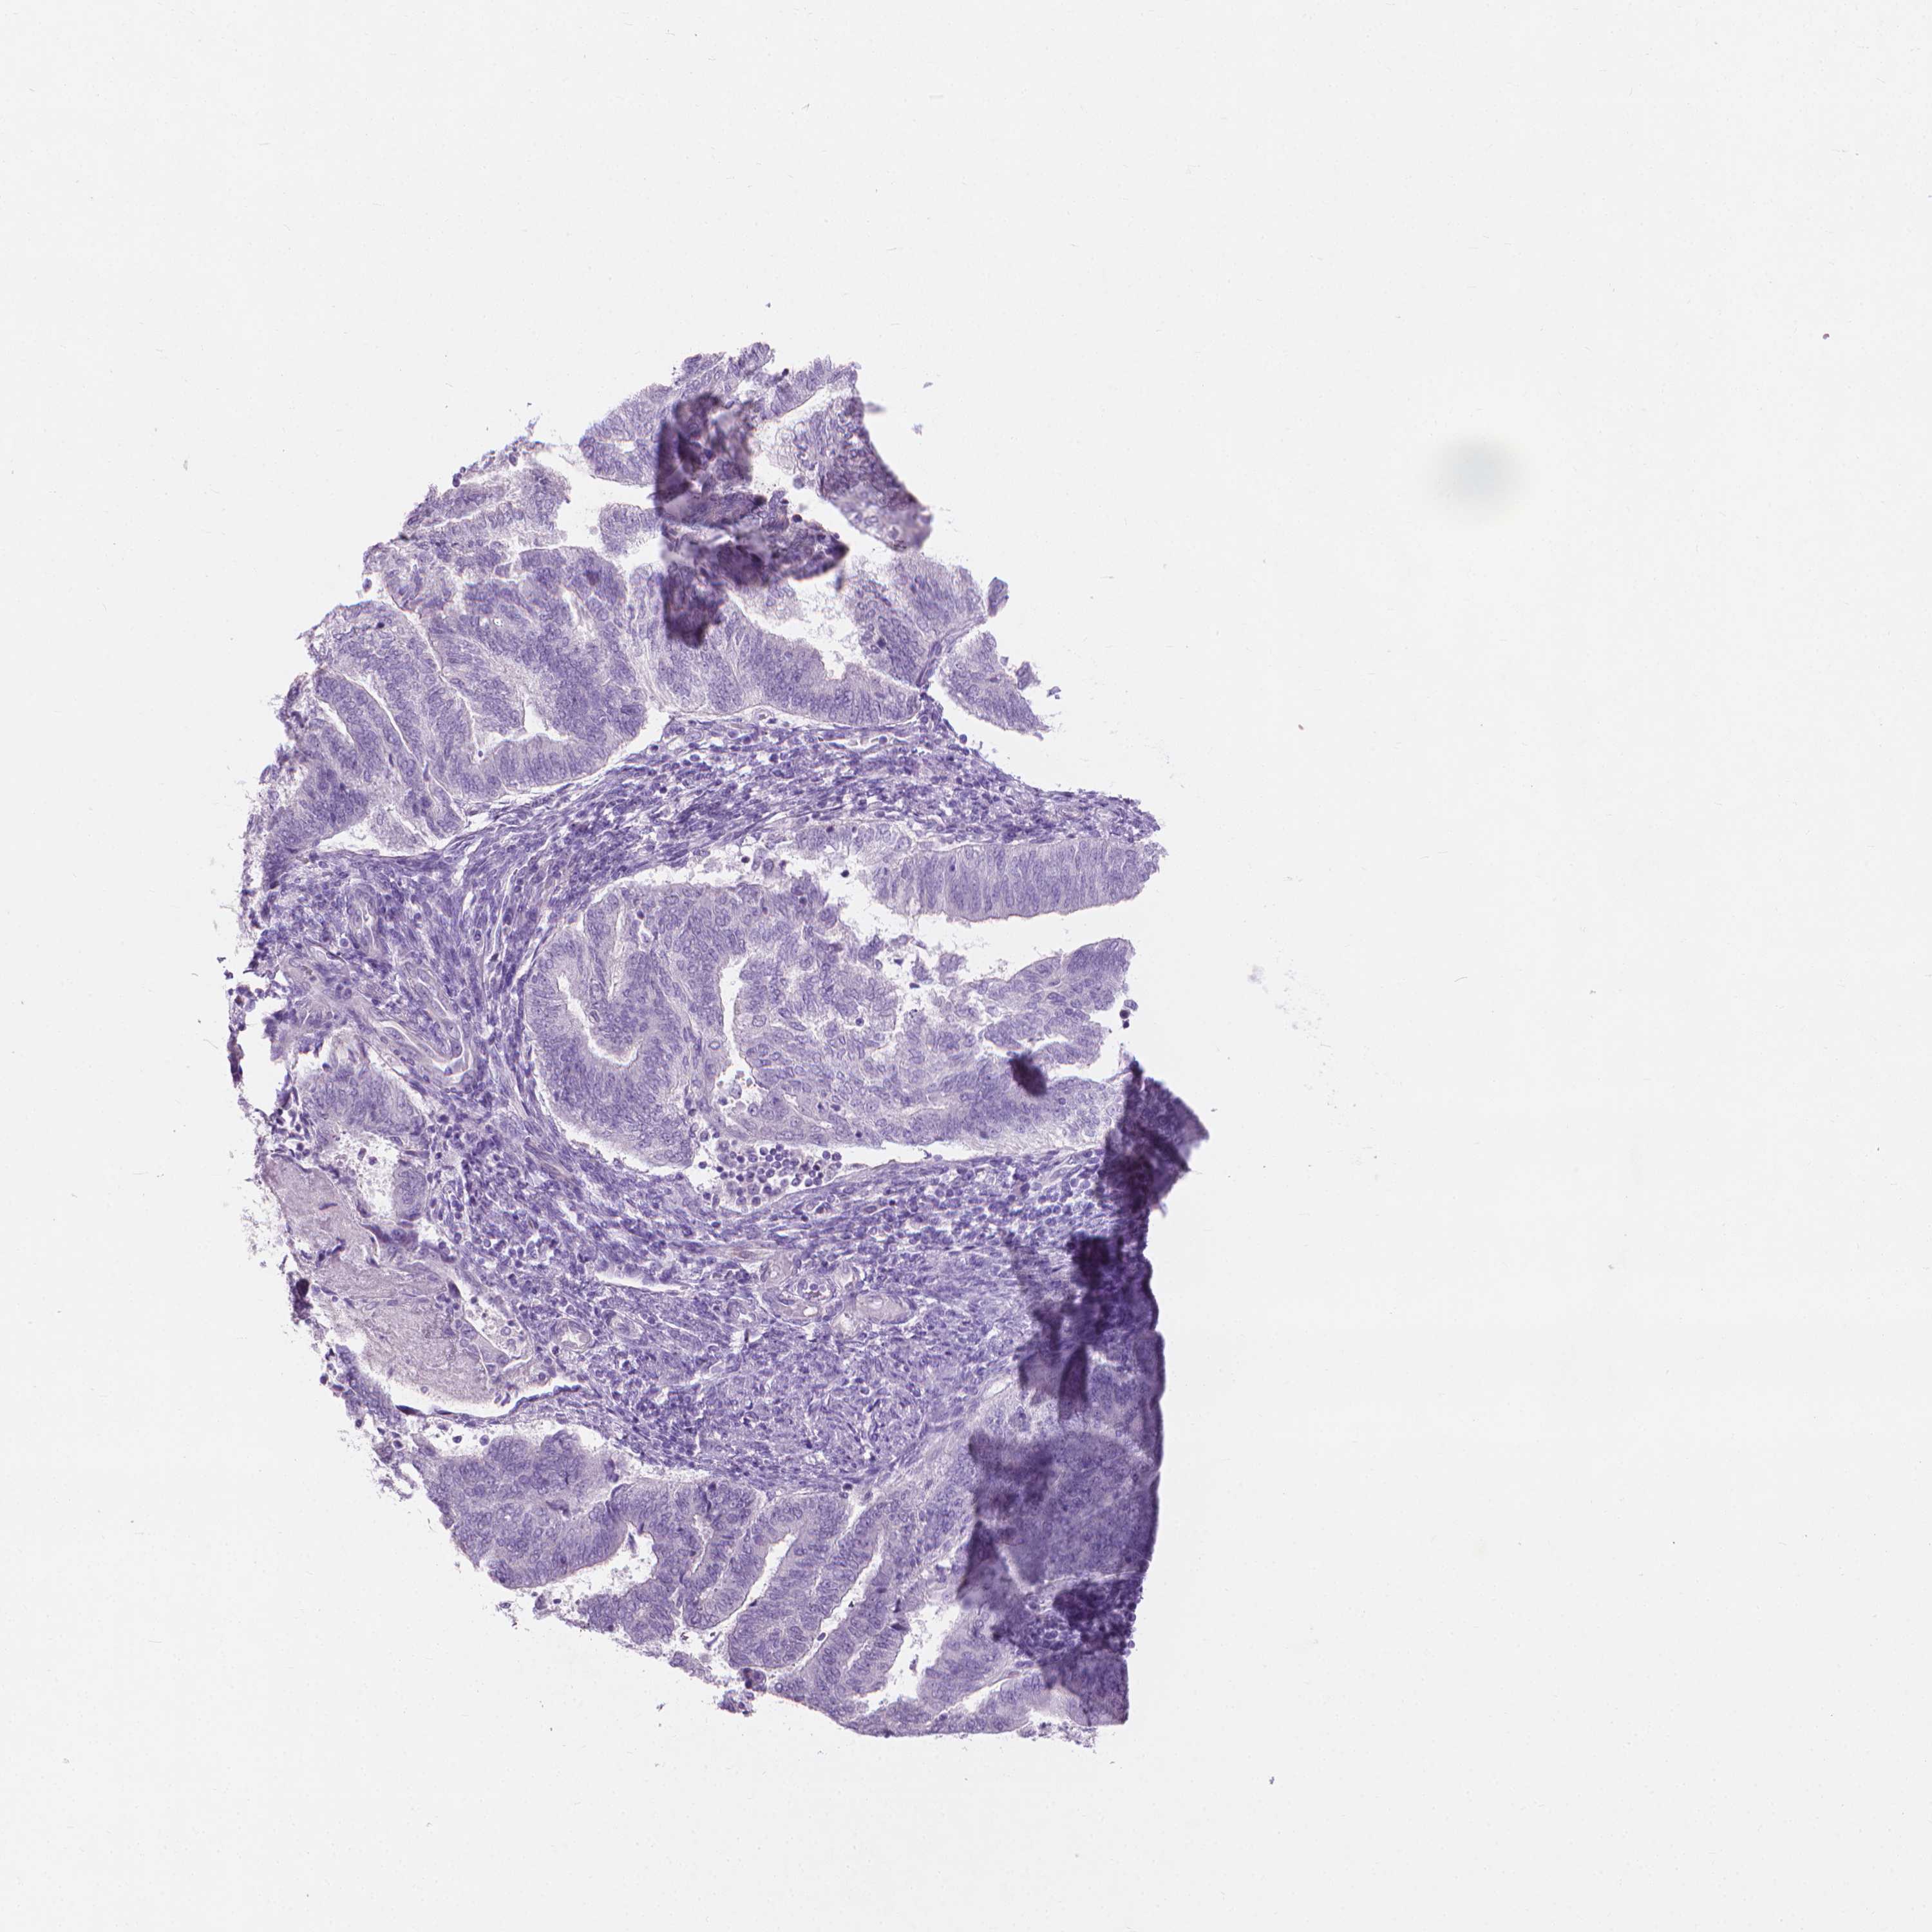

ENDOMETRIAL CANCER - Protein expressioni

A mouse-over function shows sample information and annotation data. Click on an image to view it in a full screen mode. Samples can be filtered based on level of antibody staining by selecting one or several of the following categories: high, medium, low and not detected. The assay and annotation is described here.

Note that samples used for immunohistochemistry by the Human Protein Atlas do not correspond to samples in the TCGA dataset.

Antibody stainingi

Antibody staining in the annotated cell types in the current human tissue is reported as not detected, low, medium, or high, based on conventional immunohistochemistry profiling in selected tissues. This score is based on the combination of the staining intensity and fraction of stained cells.

Each image is clickable and will lead to virtual microscopy that enables deeper exploration of all samples and also displays staining intensity scores, fraction scores and subcellular localization as well as patient and tissue information for each sample.

Antibody HPA044031

Staining

High

Medium

Low

Not detected

Intensity

Strong

Moderate

Weak

Negative

Quantity

>75%

75%-25%

<25%

None

Location

Nuclear

Cytoplasmic/membranous

Cytoplasmic/membranous,nuclear

Adenocarcinoma, NOS

Adenocarcinoma, metastatic, NOS